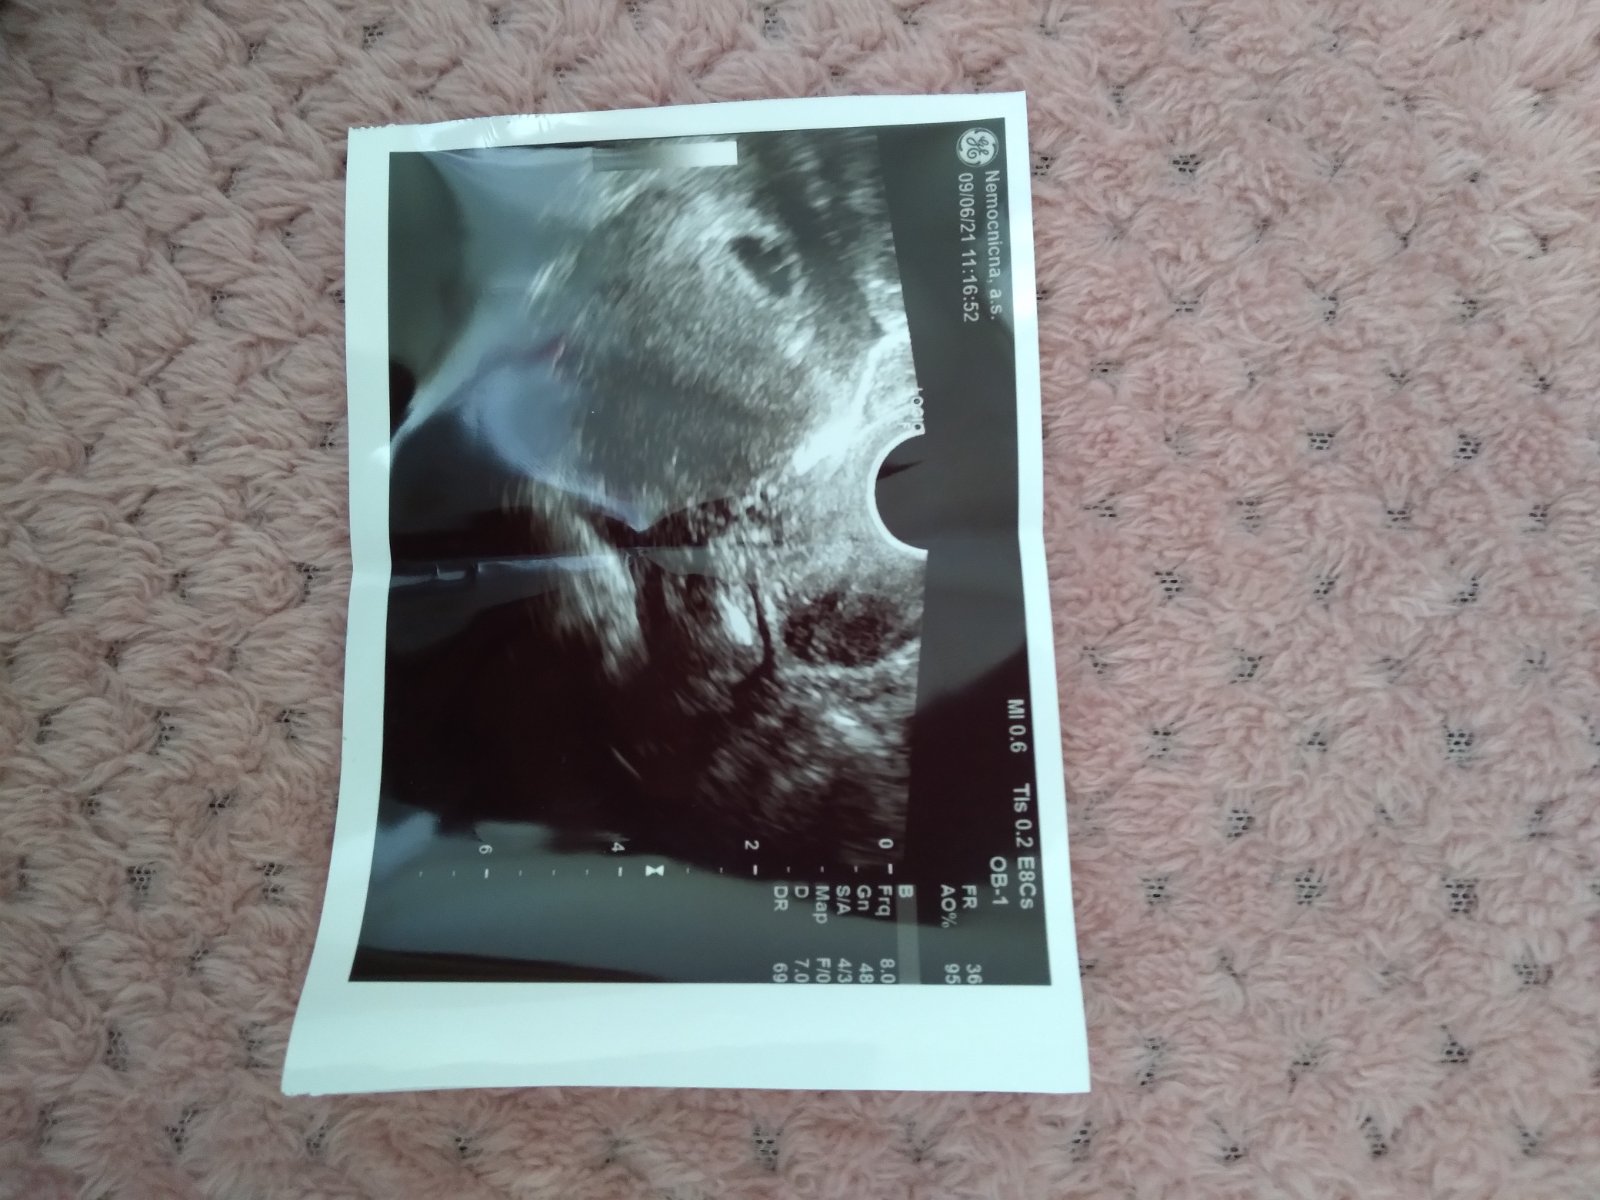

Ahojte tak dnes som bola na vyšetreni u lekára, potvrdil teda že je to uhniezdene v mateternici vďaka bohu pretože som mala veľké obavy keďže som mala v decembri mimo mateternicove .Povedal mi iba toľko že týždne zodpovedajú tomu čo vidí

Nevidel ešte plod na kontrolu idem až o mesiac v koľkom TT by mal byť vidno plod?ja som dnes 5+6ttpodla poslednej ms

Veľmi záleží aj od kvality ultrazvuku. Mne bolo vydno v 6tt + 1 deň gestačný vak, embryo akcia srdiečka. Ale je to veľmi individuálne. Plod uvidíš najskôr od 9tt vtedy sa embryo mení na plod. Od 3tt do 8tt môže byť vidno embryo, najskôr však od 5tt - 6tt na USG. @ingrida1127 držím ti palce .